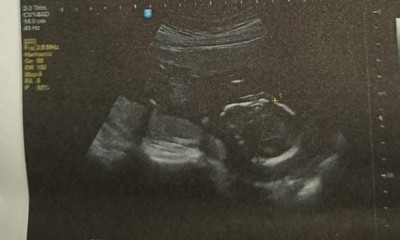

18 haftalık Olduk Ama Hala Öğrenemedik

Sizler kaçıncı Haftada öğrendiniz Bide Tahmin Alabilirmiyim

Fotoğraftan bişey anlaşılmıyor ki hem doktor bile göremediyse bizim görmemiz pek zor :)